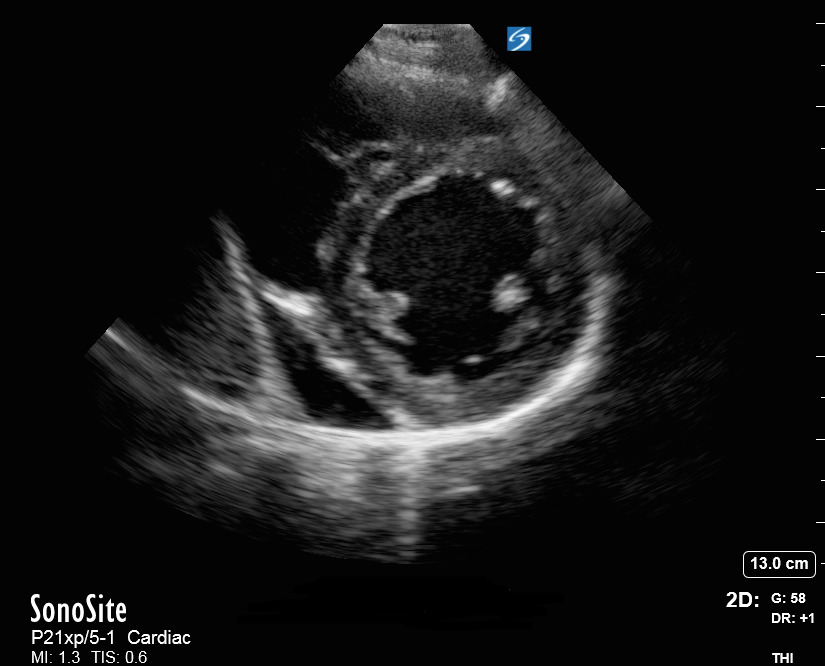

心臓の傍胸骨短軸(PSAX)画像の表示